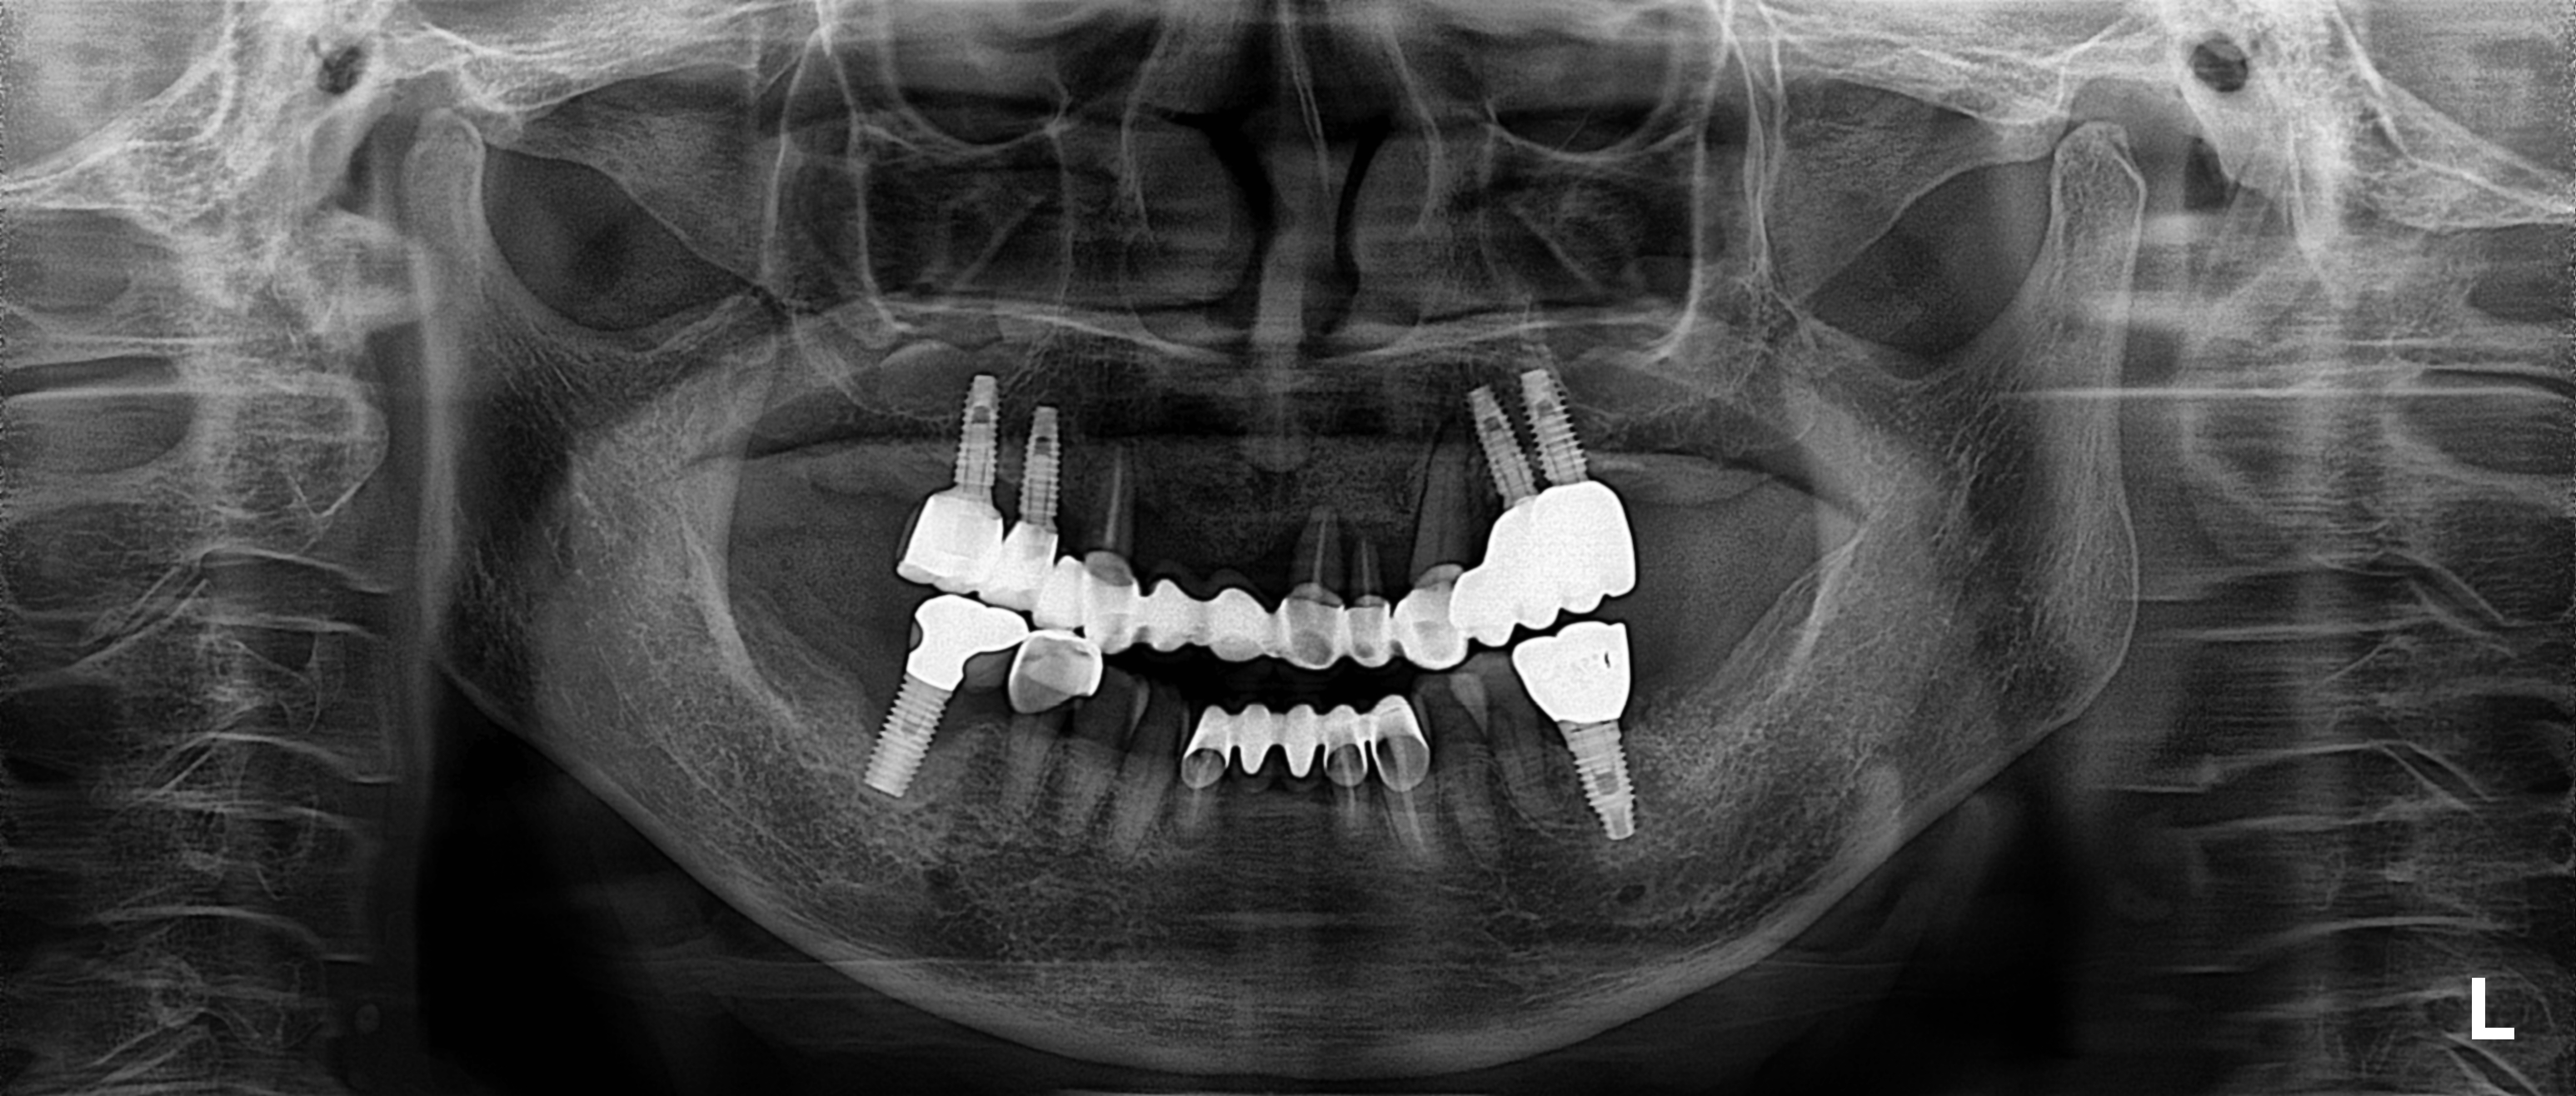

아래 케이스는 우측 임플란트를 오래전에 심었던 70대환자분입니다.

그렇기 때문에 6개월에 한번씩은 치과에 내원하여서 정기점검 및 파노라나 엑스레이 체크를 받아야 합니다.